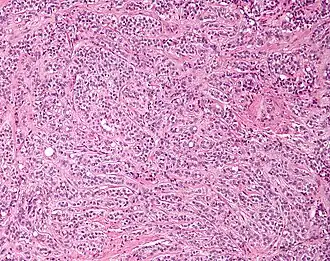

Micrograph of a Sertoli cell tumour. H&E stain.

A Sertoli cell tumour, also Sertoli cell tumor (US spelling), is a sex cord–gonadal stromal tumour of Sertoli cells. They can occur in the testis or ovary. They are very rare and generally peak between the ages of 35 and 50. They are typically well-differentiated and may be misdiagnosed as seminomas as they often appear very similar.[1]

Microscopy and immunohistochemistry are the only way to give a definitive diagnosis, especially when there is a suspected seminoma.[3]